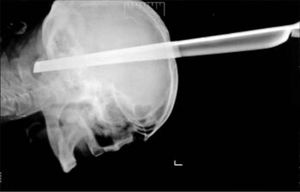

A Serbian man who was injured during a bar fight probably wished all he had to worry about was fixing a broken tooth – after his brain was impaled by the metal leg of a stool. The leg spearing 11cm (4.3in) into his brain. Doctors are flabbergasted at how the man could so easily overcome such an injury. Police and the medical professionals tending to him have no idea how the leg came to puncture his head because he arrived at the hospital with no paperwork. Lead neurosurgeon added: ‘We removed the metal body from the patient’s head without complications. ‘The man spent two weeks in intensive care in a serious but stable condition.' FOLLOW us @medicalpedia for more extreme medical cases!